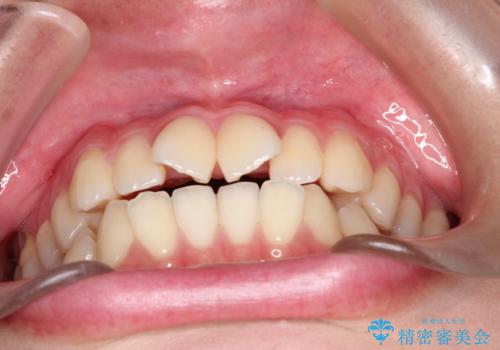

インビザラインによる非抜歯矯正 ガタガタな歯並びを整った歯並びへ

また人前でお話する機会もあるとのことだったので、目立たない装置をご希望されインビザラインで治療を行うこととなりました。

使用時間を守っていただけたので、スムーズに治療を終わることができました。